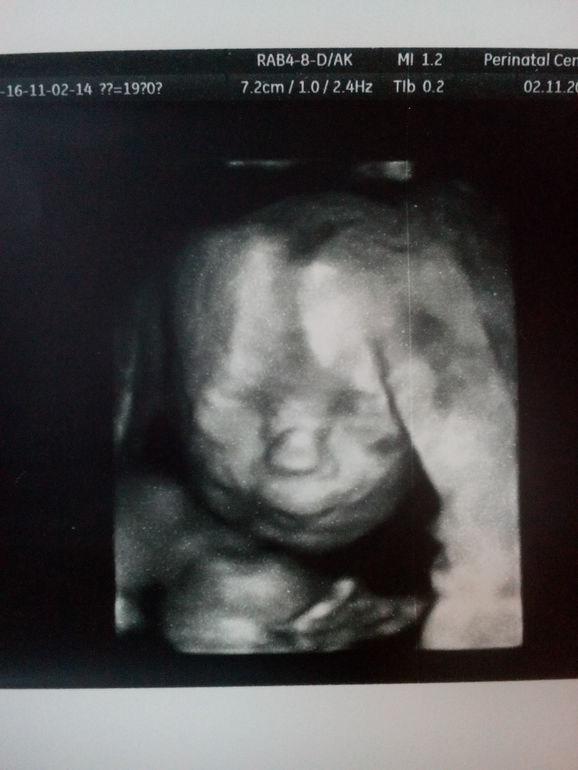

По УЗИ у нас все хорошо,,,уже опережаем по замерам почти на неделю.и будет у нас-СЫНОК)))

САМА видела воочию его писюнчик и кокошки)))на 3 д так вообще вылитый старший сынок)))губки так же делает) и нос- курнос)))